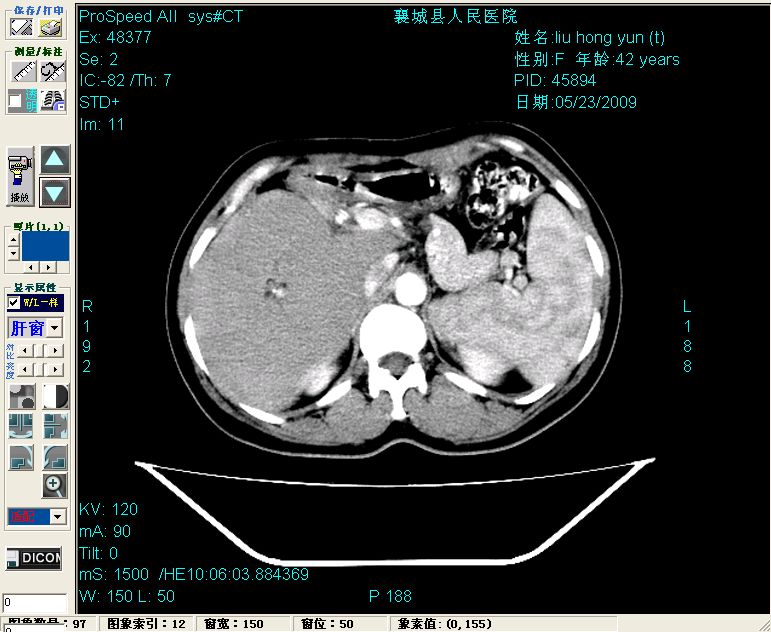

平扫:

平扫左肝外叶体积显著减小,左肝外叶见多房囊性低密度区,左肝实质及右肝前叶浅表实质呈低密度改变,左肝及右肝前叶胆管扩张,脾大

2左肝及右肝前叶表现考虑胆囊摘除术后所致的肝动门脉瘘形成,慢性纤维组织炎性增生.不完全除外左肝胆管细胞癌